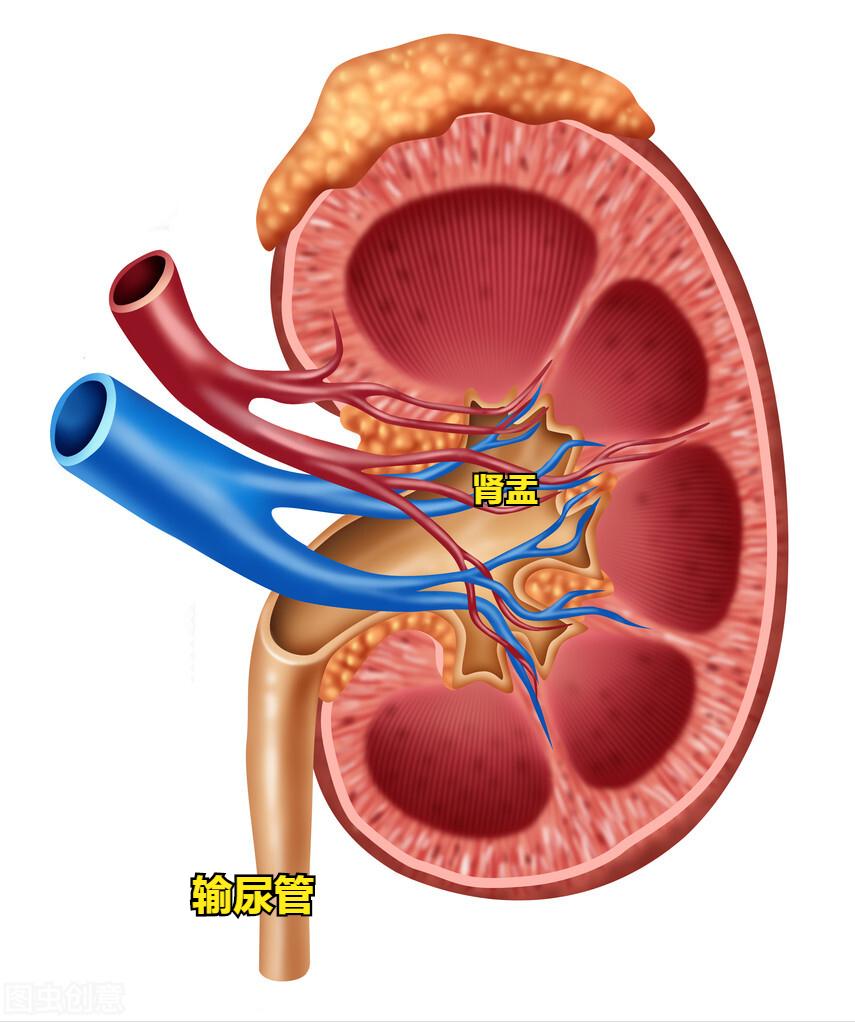

肾结石一般躲在我们的肾窦的各个角落内。

在任何时候都有可能自行掉下来,顺着输尿管往下走。

看,上面那个结石就已经走到输尿管了。

输尿管内径约0.5-1cm,较小的结石可以通过,但对于较大的结石就没有通过的可能,毕竟门就那么大。